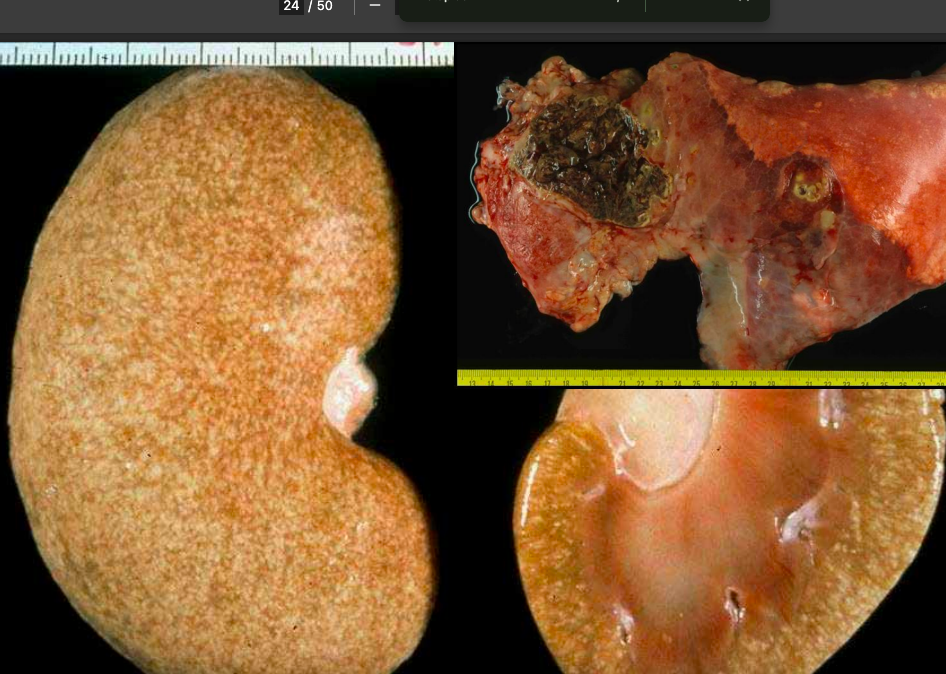

Amiloidosis renal:

Macroscopicamente se ve un riñon firme (NO FRIABLE), de mayor tamaño y con manchas grisaceas jaspeadas

Aspecto microscopico del amiloide Eosiinofilo, eosinofilo homogeneo refringente. En el rojo congo se ve rojo, con luz polarizada encima se ve birrefringente

Al llenarse el espacio del glomerulo con amiloide se pierde la funcionlidad del riñon.